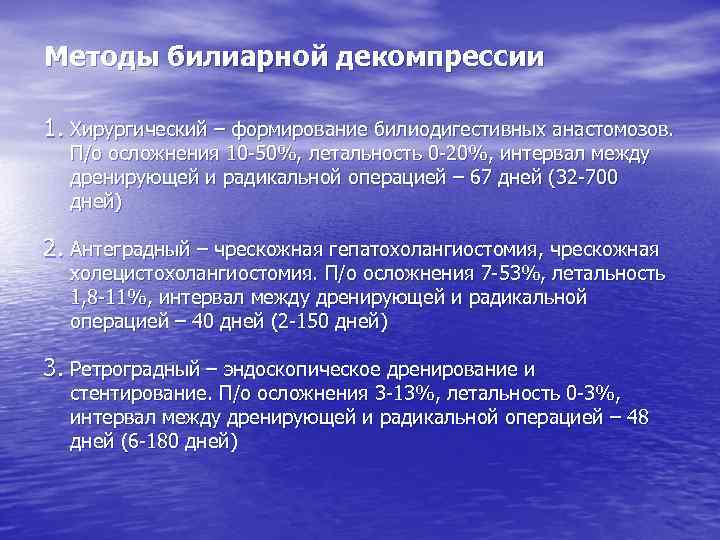

Методы билиарной декомпрессии 1. Хирургический – формирование билиодигестивных анастомозов. П/о осложнения 10 -50%, летальность 0 -20%, интервал между дренирующей и радикальной операцией – 67 дней (32 -700 дней) 2. Антеградный – чрескожная гепатохолангиостомия, чрескожная холецистохолангиостомия. П/о осложнения 7 -53%, летальность 1, 8 -11%, интервал между дренирующей и радикальной операцией – 40 дней (2 -150 дней) 3. Ретроградный – эндоскопическое дренирование и стентирование. П/о осложнения 3 -13%, летальность 0 -3%, интервал между дренирующей и радикальной операцией – 48 дней (6 -180 дней)